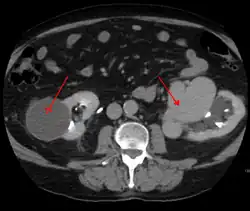

AVMs can occur in various parts of the body:

- brain (cerebral AV malformation)

- spleen[13]

- lung[14][15]

- kidney[16]

- spinal cord[17]

- liver[18]

- intercostal space[19]

- iris[20]

- spermatic cord[21]

- extremities – arm, shoulder, etc.